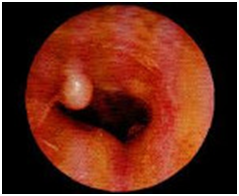

Экзостозы наружного слухового прохода

Экзостозы наружного слухового прохода – это доброкачественные костные новообразования, которые возникают на барабанной части височной кости. Клинические проявления заболевания развиваются только при их сильном разрастании; включают в себя снижение остроты слуха, шум в ушах, головную боль, реже – постепенно нарастающую локальную болезненность. В процессе диагностики используются анамнестические сведения, результаты отоскопии и аудиометрии, при необходимости – компьютерной томографии. Лечение показано только при выраженном разрастании экзостозов с появлением клинической симптоматики, заключается в хирургическом удалении образований.

• Отоскопия. Визуальный осмотр слухового прохода обоих ушей позволяет обнаружить на задневерхней стенке одно или несколько возвышений с широкой основой, покрытых нормальной неизмененной кожей. Реже экзостозы имеют острые края, форму шара или гриба. Поверхность обычно гладкая. При надавли вании пуговчатым зондом определяется высокая плотность, характерная для костной ткани.